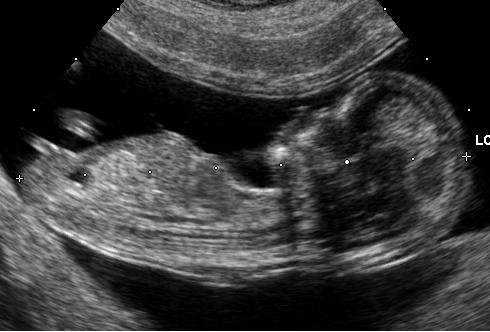

Your pregnancy timing is measured by the doctor/gynecologist using gestational age. It is calculated on the day of your last menstrual period (LMP). So, LMP is the date when you first started your last periods. Many women confuse the gestational age. Most calculate the day they think the conception occurs (mostly on the 14th day from the first day of periods). But, pregnancy is measured three to four weeks before you get pregnant (starting from the first day of your last periods). So, a full term pregnancy is calculated as 40 weeks from your LMP. If your periods are not regular or you do not remember the date, then your doctor uses an ultrasound scan to find the gestational age.

Your baby is very small (size of a BB pellet) and resembles a tadpole. Once you have confirmed the pregnancy with the home test, you need to book an appointment with your doctor. The doctor checks if the implantation has occurred in the uterus. In some cases, the fertilized egg does not reach the womb and starts growing in the Fallopian tube. The condition known as ectopic pregnancy can put your life in danger. Therefore, an ultrasound can detect the implantation and also the heartbeat. Remember, your child is vulnerable between the fourth and fourteen weeks (days 17-56). So, any problem can affect growth. So, you need to maintain caution during the time period.

Once you reach fourteen weeks of your pregnancy, you enter the second trimester. Your baby in the womb undergoes major development. But, when you undergo an ultrasound scan, the babyâs head looks larger than the body. You can schedule for a scan to listen to the strong heartbeat of your baby. At the end of the 16th week, you can ask your doctor about genetic testing. It is necessary for parents who already have a child with a genetic disorder or have family members with the problem. As the pregnancy symptoms may not indicate the overall health of the child, you need to ask your doctor about the necessary tests.

It is an important and busy month for your child. Your baby starts developing eyebrows, eyelashes, taste buds, and blood cells. During the routine ultrasound scan, you can see the baby opening its eyes. The finger and toe prints become visible during the sixth month. You can feel your baby responds to sounds. Therefore, the baby moves or increases the pulse.